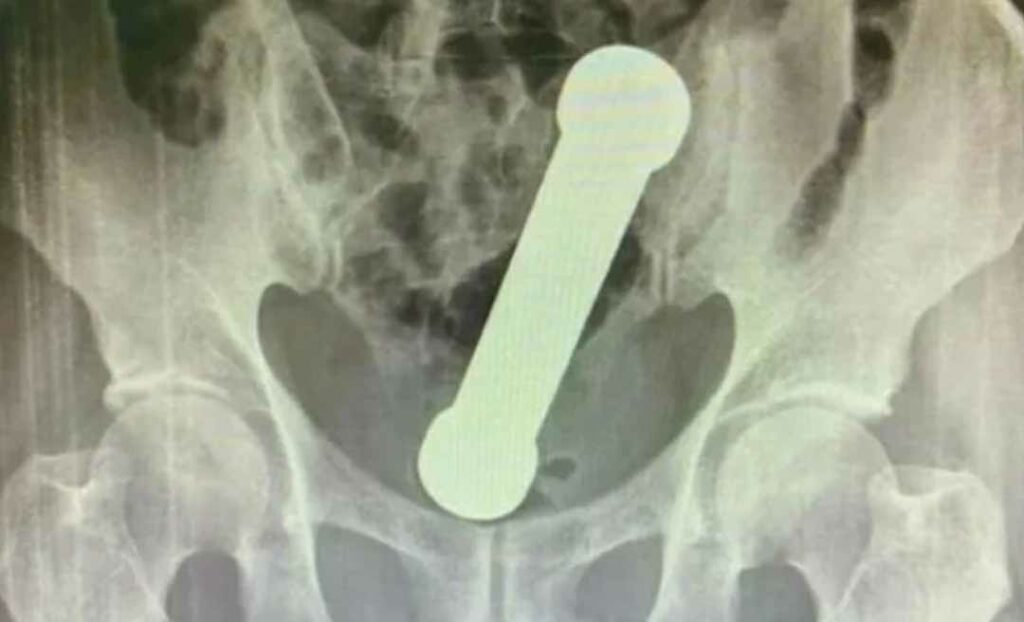

Segundo o artigo, o homem de identidade não revelada chegou ao hospital com dores que duravam dois dias e pediu para ser examinado. Os médicos decidiram pedir raio-x da região abdominal e foram surpreendidos com a presença “de um corpo estranho em forma de haltere de exercício”, diz o relatório.

Ao realizarem um exame de radiografia, os médicos encontraram dentro do homem um peso de dois quilos, de cerca de 20 centímetros de comprimento, como os instrumentos de academias utilizados para exercícios de braço.